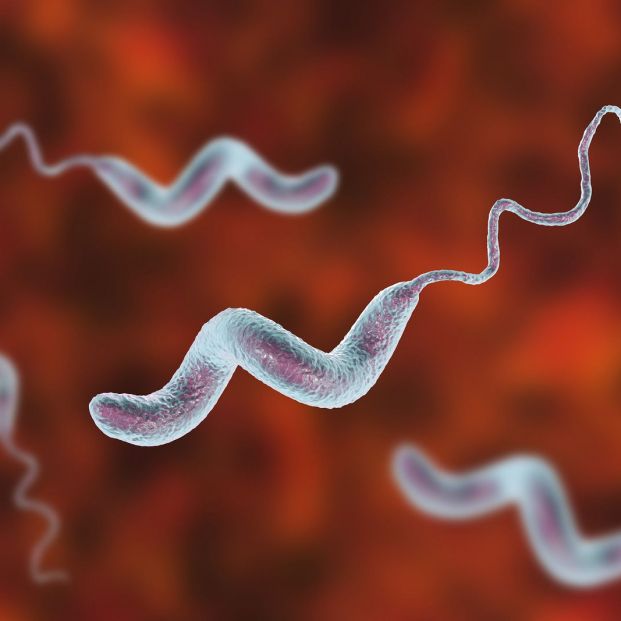

Кампилобактер фетус: патогенез и инфекции